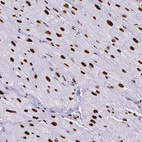

Immunohistochemical staining of human endometrium, heart muscle, kidney and pancreas using Anti-NONO antibody HPA054559 (A) shows similar protein distribution across tissues to independent antibody HPA054094 (B).